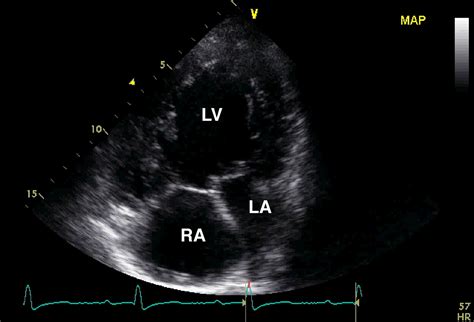

Receiving a diagnosis of Double Inlet Left Ventricle (DILV) can be overwhelming for families and patients alike. As a complex form of congenital heart disease, understanding the mechanics of how this condition affects cardiac function is the first step toward effective management. DILV is categorized as a single ventricle defect, meaning that instead of the heart having two functional pumping chambers, one chamber is significantly underdeveloped or effectively non-functional. In this specific anomaly, both the mitral and tricuspid valves—which usually empty into two separate ventricles—lead into a single, dominant left ventricle. This anatomical structure causes oxygen-rich blood and oxygen-poor blood to mix, forcing the heart to work harder to circulate blood throughout the body.

To grasp the implications of Double Inlet Left Ventricle, it is helpful to visualize the normal circulatory system. In a typical heart, the right side pumps oxygen-poor blood to the lungs, while the left side pumps oxygen-rich blood to the rest of the body. In a patient with DILV, the blood from both the right and left atria flows into the same large ventricular chamber. Because this single chamber is responsible for pumping blood to both the lungs and the entire body, the heart faces a unique challenge in maintaining systemic pressure and lung circulation.

• double inlet lv echo